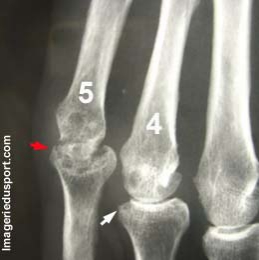

Fracture Cartilage De Conjugaison, Radius Distal

radiologie conjugaison distale salter distal déplacement ulna

Fracture Isolée Radius